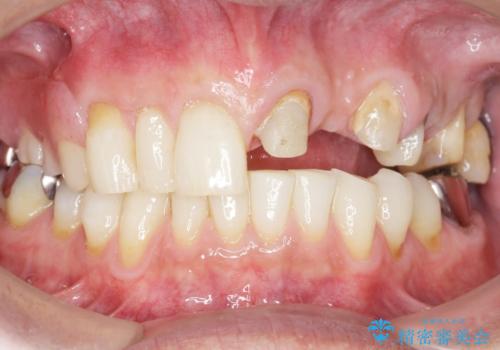

ご希望により最終補綴前にホームホワイトニングを行っております。

最終補綴前に右上321の結合組織移植術(CTG)を希望されたため、大元院長に行って頂きました。

牽引により歯の保存が可能となり、ブリッジによる補綴を行うことができました。

健全歯質を歯肉縁上に出すためにしっかり挺出させたことで歯根長が短くなりましたが、仮歯で十分に保定した結果動揺度Ⅰ程度となり、ブリッジの支台歯にすることが可能と判断しました。

患者様には「抜歯適応の歯を残せて嬉しいし、とても丁寧に治療して頂けた」と大変喜んで頂けました。

クラウンの種類:オールセラミッククラウン スタンダード